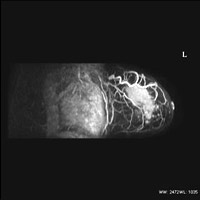

AIR Recon DL画像の一例

造影剤を用いた乳房検査